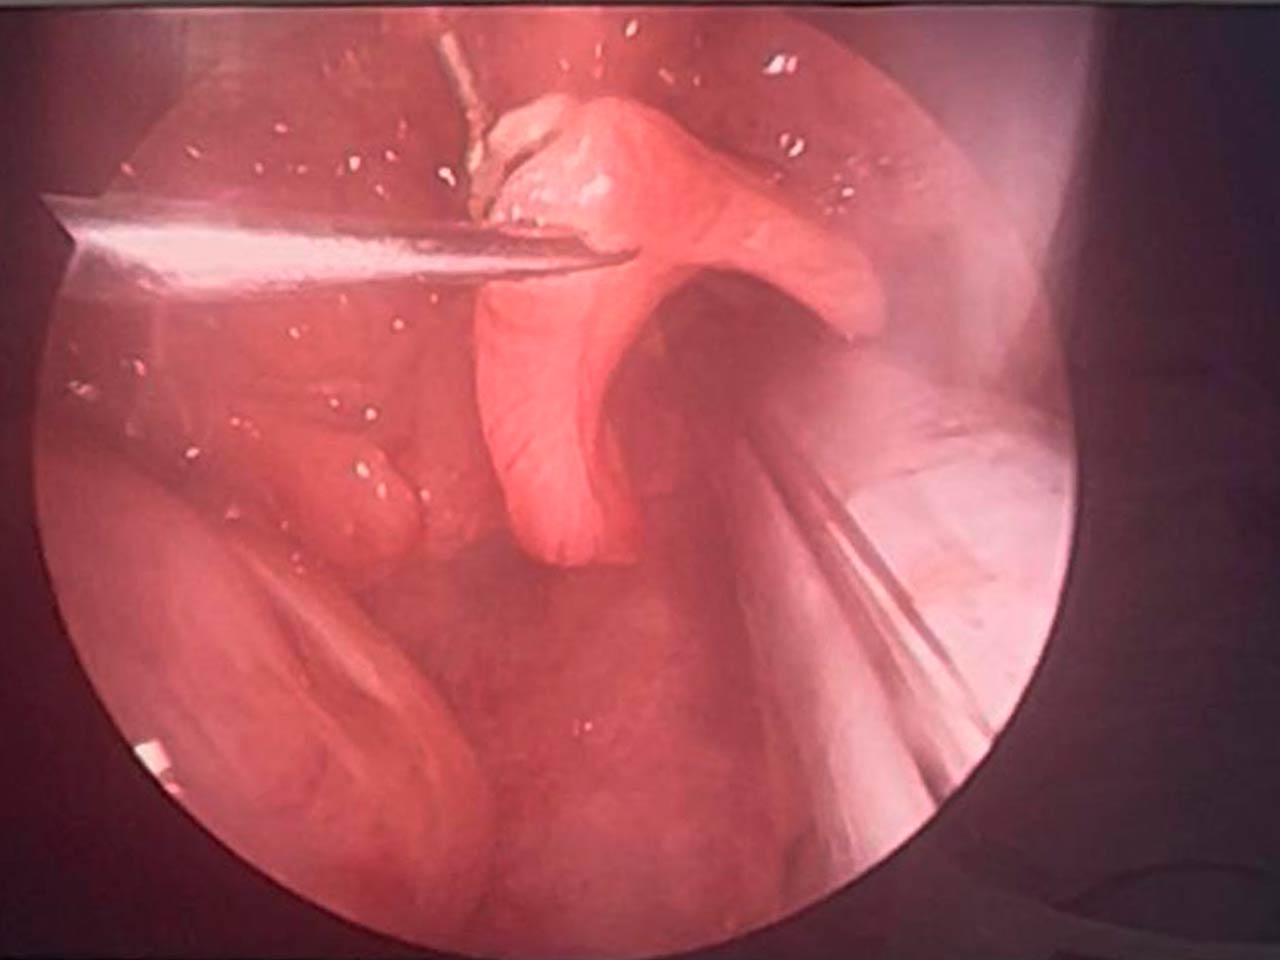

- Evaluación endoscópica de nariz, faringe y laringe

- Microcirugía Laringea Y Fonocirugía: Tratamiento de parálisis de cuerdas vocales

- Laringoplastias: resección de lesiones estenosantes o colocación de tubo en t.